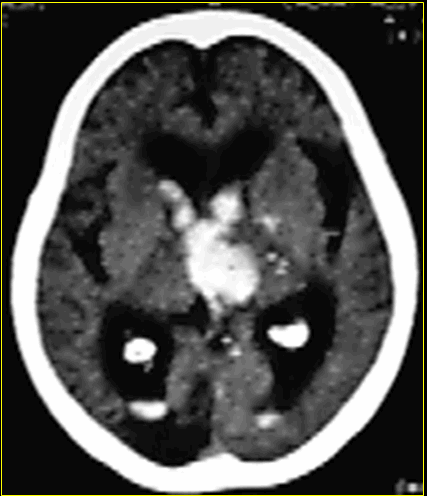

- Xuất huyết não và não thất

Xuất huyết não và não thất

Xuất huyết trong não thất thường liên quan với máu tụ trong não, xuất huyết dưới màng nhện, máu tụ dưới màng cứng, Các bệnh nhân này thường có phân loại 3 hoặc nặng hơn.